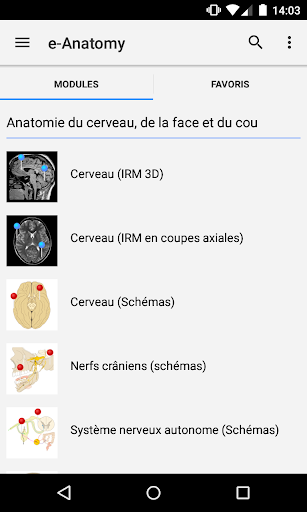

IMAIOS e-Anatomy adalah atlas anatomi manusia untuk dokter, ahli radiologi, mahasiswa kedokteran, dan teknisi radiologi. Dapatkan cuplikan lebih dari 26.000 gambar medis dan anatomi secara gratis sebelum berlangganan atlas anatomi manusia terperinci kami.

e-Anatomy didasarkan pada atlas daring IMAIOS e-Anatomy yang telah memenangkan penghargaan. Bawalah referensi anatomi manusia terlengkap, ke mana pun Anda pergi, di perangkat seluler atau tablet Anda.

Baru : Sekarang Anda dapat memfilter modul berdasarkan wilayah atau jenis konten sehingga Anda dapat menemukan modul yang Anda cari lebih cepat.